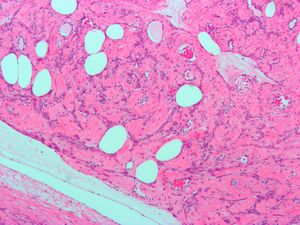

| Uterine lipoleiomyoma, a type of leiomyoma. H&E stain. | |

A rare form of these tumors is lipoleiomyoma[2].

Uterine lipoleiomyoma, a type of leiomyoma. H&E stain.